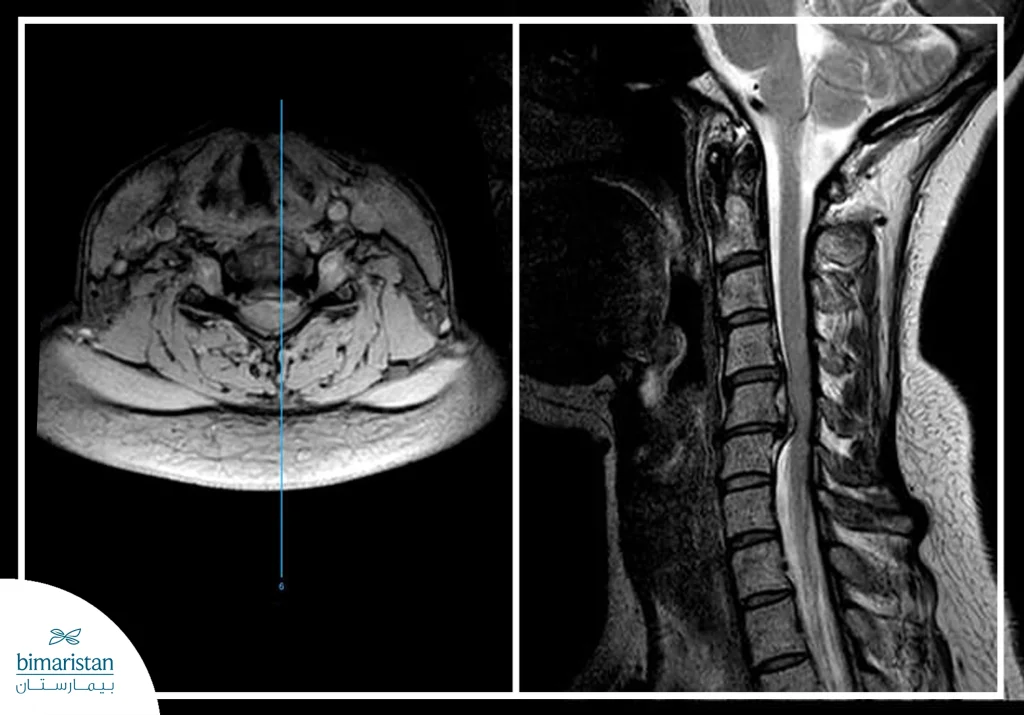

- Magnetic Resonance Imaging (MRI): MRI is the most sensitive type of imaging for examining intervertebral discs, as it is able to show the discs, neighboring soft tissues and surrounding nerves much more clearly than other imaging modalities.